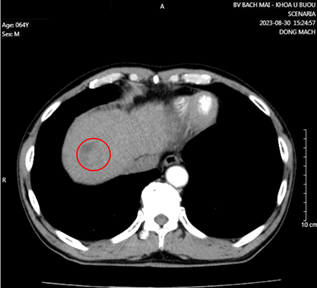

Bệnh nhân khám tại Khoa Khám bệnh, Bệnh viện Bạch Mai, chụp cắt lớp vi tính lồng ngực phát hiện khối, nốt ở nhu mô phổi và khối nhu mô gan. Bệnh nhân sau đó được chuyển đến Trung tâm Y học hạt nhân và Ung bướu.

Nhu mô hạ phân thùy VII có vài khối, nốt kích thước lớn nhất 33x26mm giảm tỷ trọng trước tiêm, ngấm thuốc thì động mạch (vòng tròn đỏ), thải thuốc thì tĩnh mạch cửa (vòng tròn).

Căn cứ vào các kết quả cận lâm sàng, xét nghiệm… bệnh nhân được chẩn đoán xác định ung thư phổi trái không tế bào nhỏ di căn phổi EGFR (+), giai đoạn IV cT3N0M1 – Ung thư đường mật type ống nhỏ di căn hạch rốn gan, giai đoạn IIIB cT2N1M0/viêm gan B.